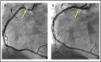

Se realizó una tomografía axial computarizada (TAC) cardiaca en las primeras 24h, en la que se observó una lesión severa en CD ostial con salida ligeramente por encima de la UST y se confirmó también el origen anómalo del TCI, con trayecto interarterial (fig. 1). Posteriormente, en una coronariografía electiva se logró sondar selectivamente la CD, que ya en ese momento estaba permeable y presentaba una lesión crítica a nivel ostial donde se implantó un stent farmacoactivo, con resultado satisfactorio (fig. 2). Tras la revascularización completa se apreció normalización de la función biventricular y el paciente pudo ser dado de alta sin incidencias.

A)Aortograma en proyección oblicua anterior izquierda que demuestra los 3 senos de Valsalva y la aparente ausencia (?) de la coronaria derecha. De forma no selectiva se rellena parcialmente el tronco de la coronaria izquierda (flechas) que nace algo por encima de la unión sinotubular. B)Tomografía axial computarizada que demuestra una placa calcificada (flecha discontinua) en el ostium de la coronaria derecha que ya ha recuperado flujo anterógrado (flecha). C)Salida de la coronaria izquierda con trayecto intraarterial (flechas amarillas).